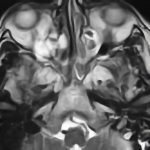

症例 '17年2月

No.

22

’17_22

'17年2月

60代

トルコ鞍部腫瘍

経鼻的下垂体

腫瘍摘出術

断層撮影

手術前

1

手術前2

手術後